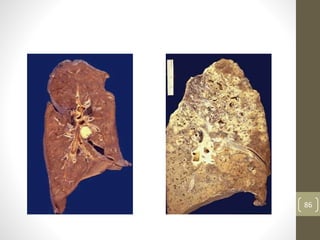

*Caseousnecrosis

• distinctive form of coagulative necrosis

• encountered most often in foci of tuberculous

infection

-The term caseous- ‘cheesy white’ gross

appearance of the area of necrosis

-microscopically-amorphous granular debris with

distinctive inflammatory border known as

granulomatous reaction